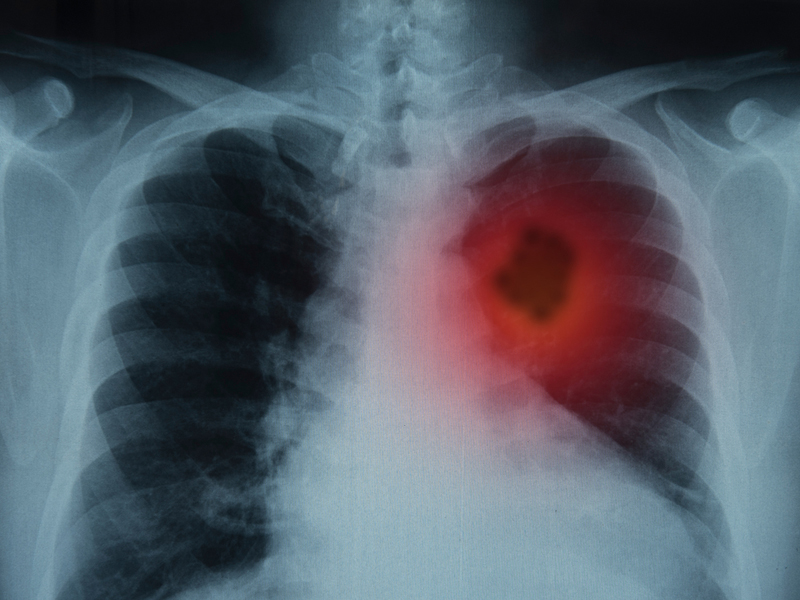

| 中國研究人員在《細胞》雜誌上發表報告,指出一種新發現的蝙蝠冠狀病毒與新冠病毒通過相同的途徑入侵人體。這意味著蝙蝠冠狀病毒未來可能會傳播給人類。 蝙蝠病毒含弗林蛋白酶裂解位點 研究指出,蝙蝠病毒含有一種被稱為弗林蛋白酶(furin)裂解位點的特徵,這有助於病毒通過細胞表面的蛋白進入人體細胞。然而,研究人員強調,蝙蝠病毒有一定的局限性,不會像新冠病毒那樣容易進入人體細胞。 研究引發恐慌,疫苗生產商股價上漲 雖然蝙蝠病毒尚未在人體內檢測到,但這項研究報告引發了一些恐慌,並推動部分冠病疫苗生產商的股價上漲。在 2 月 21 日股市大幅下跌的情況下,輝瑞、莫德納(Moderna)、諾瓦瓦克斯(Novavax)的股價分別上漲 1.5%、5.3% 及約 1%。 專家:反應過於誇張,免疫力提升降低風險 明尼蘇達大學傳染病專家麥克爾·奧斯特霍姆(Michael Osterholm)認為,人們對這項研究的反應過於誇張。他指出,與 2019 年相比,人們對類似病毒的免疫力已經提升,這可能降低再次發生大規模疫情的風險。研究也指出,蝙蝠病毒與人類細胞結合的能力較弱,因此在人群中出現的風險不應被誇大。 |